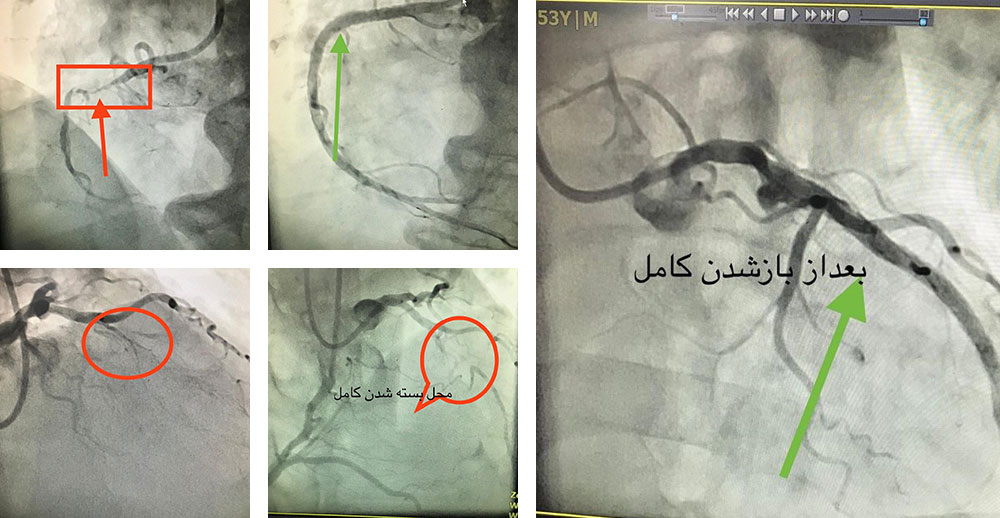

انسداد کامل رگ

انسداد کامل رگ آخرین سنگر ناگشوده ی آنژیوپلاستی بود که با تکنیک های جدید، تا ۹۰٪ امکان بازگشودگی بدون جراحی قلب باز را دارد. بیمار اول انسداد کامل رگ راست و دومی انسداد کامل رگ چپ داشتند. هر دو بیمار از طریق هر دو شریان دست راست وچپ درمان و روز بعد بی هیچ عارضه یی مرخص شدند. ایمان بیاوریم به اعجاز روش های نوین آنژیوپلاستی!